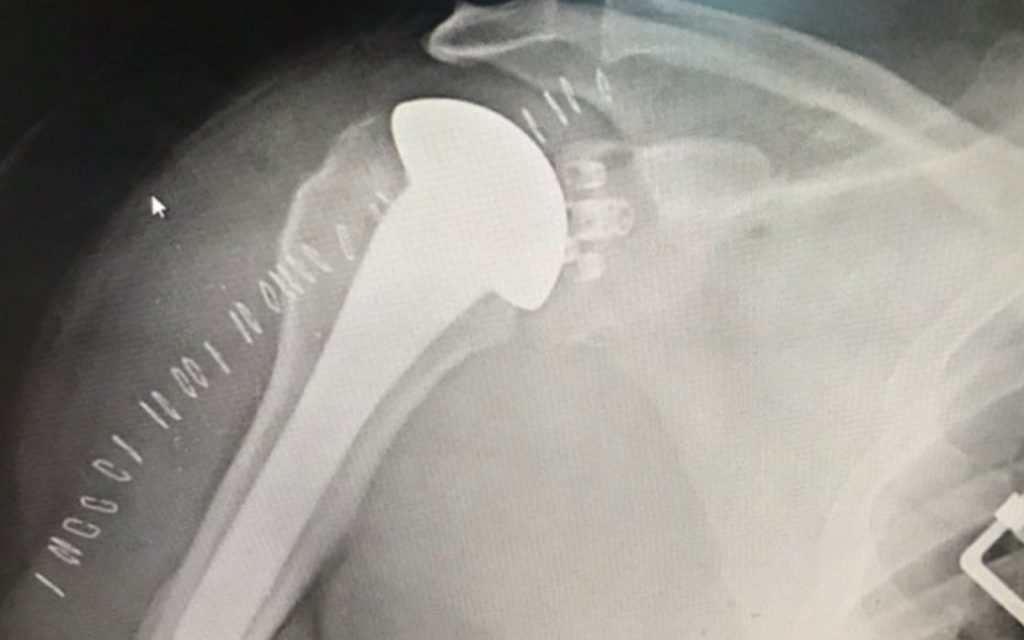

Stress Fractures After rTSA. Not Every Onlay is Created Equal.

The Effect of Lateralization on the Rotator Cuff Following Reverse Shoulder Arthroplasty

Shoulder Revision with a Platform System

Revision With a Platform System

Equinoxe Preserve Shoulder Stem

Optimizing Mini-Stem Humeral Component Design in Shoulder Arthroplasty